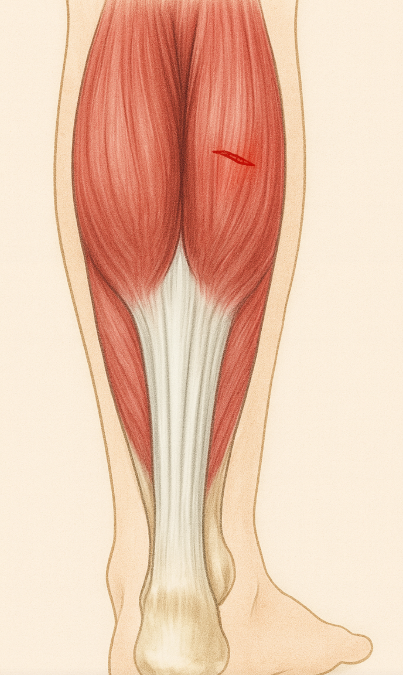

Det kan hända på en löprunda, under ett träningspass eller till och med när du reser dig snabbt ur soffan – en plötslig smärta i muskeln. Men hur vet man om det är en sträckning eller en bristning. Sträckning En sträckning innebär att muskelfibrerna dragits ut...